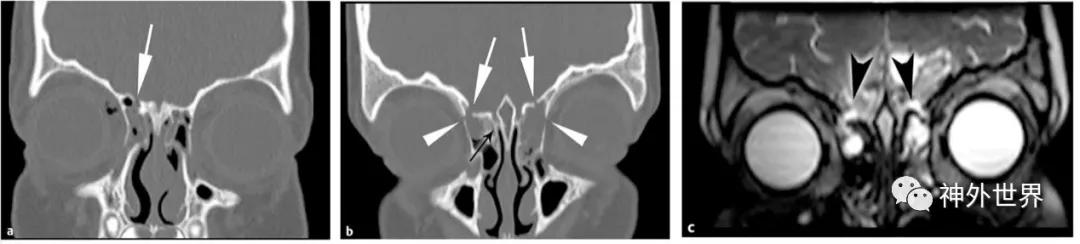

图6:筛骨骨折 。A,冠状位CT示右侧筛窦顶板(白色箭头)骨折;B,冠状位CT示双侧筛窦骨折(白色箭头)与双侧内侧眶壁骨折(白色短箭头),筛板无异常(黑色箭头);C,高分辨率T2WI示CSF漏(黑色箭头),表现为骨折线两侧的脑脊液T2高信号